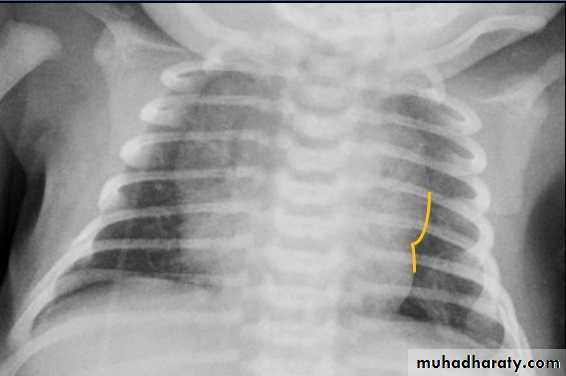

CXR of a neonate ,PA view shows thymus gland (normal finding not a disease ) with indentationsUL: Thymus Indentation sign. UR: Thymic wave sign, Lower: Thymic Sail sign

normal chest XR of the infant( normal thymus gland) Sail sign